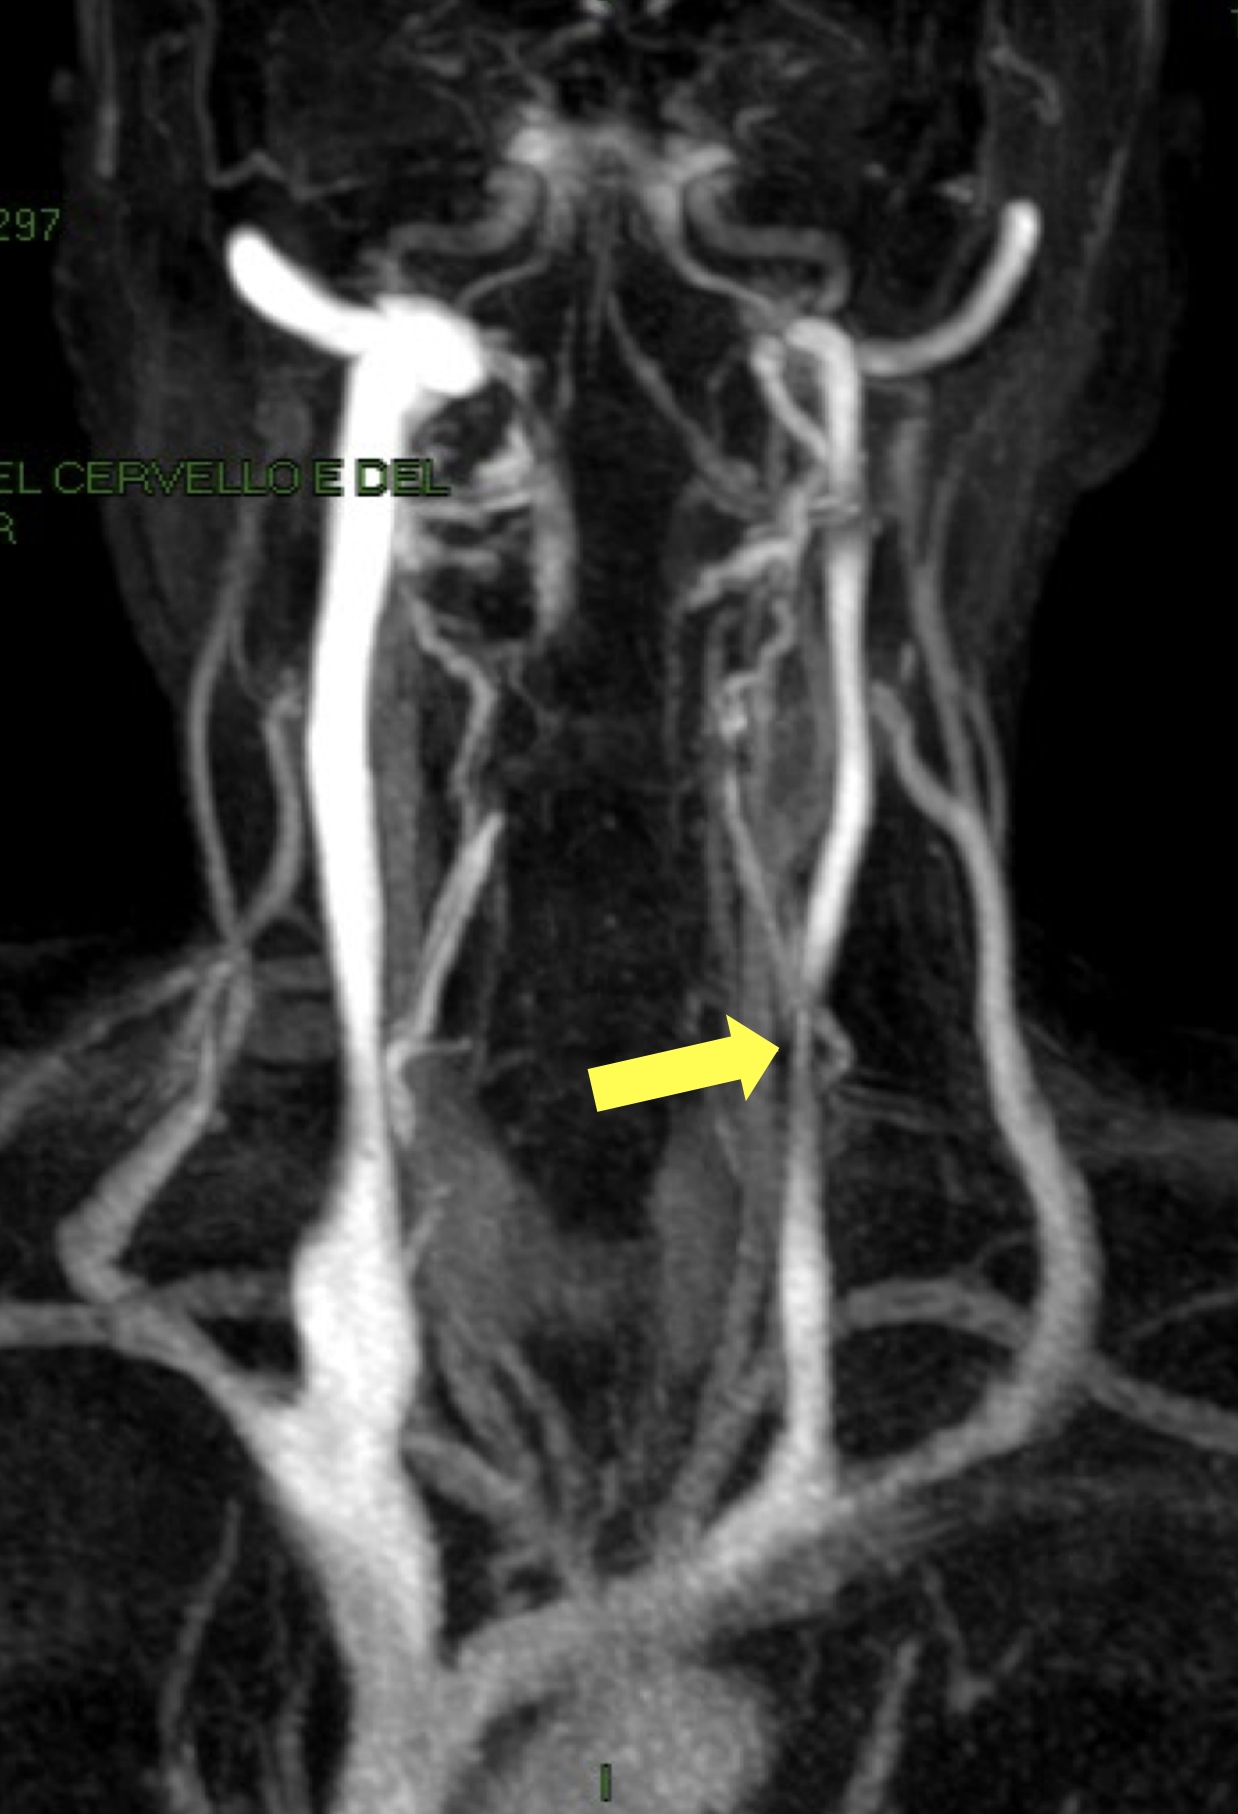

Diagnosi e trattamento dell'Insufficienza Venosa Cronica Cerebrospinale (CCSVI)